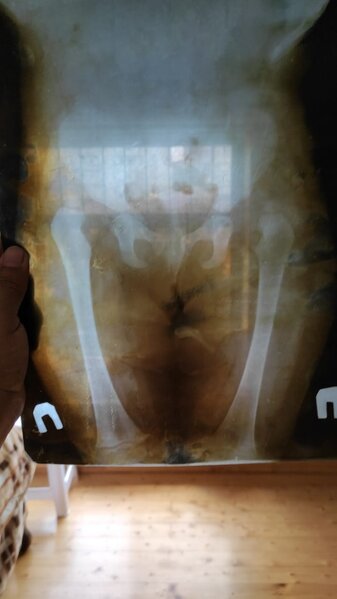

7 yaşlı Aytən Qurbanova anadangəlmə bud-çanaq oynağının hər iki tərəfli çıxığı xəstəliyindən əziyyət çəkir. O, çətinliklə yeriyir və onurğasında lordoz xəstəliyi var.

Bu barədə Aytən Qurbanovanın valideyni Sonxeber.az-a müraciətində bildirib. O, qeyd edib ki, hər iki bud çanaq oynağının əməliyyatı üçün 14000 AZN vəsait tələb olunur və ailə maddi imkansızlığa görə bu məbləği toplaya bilmir.